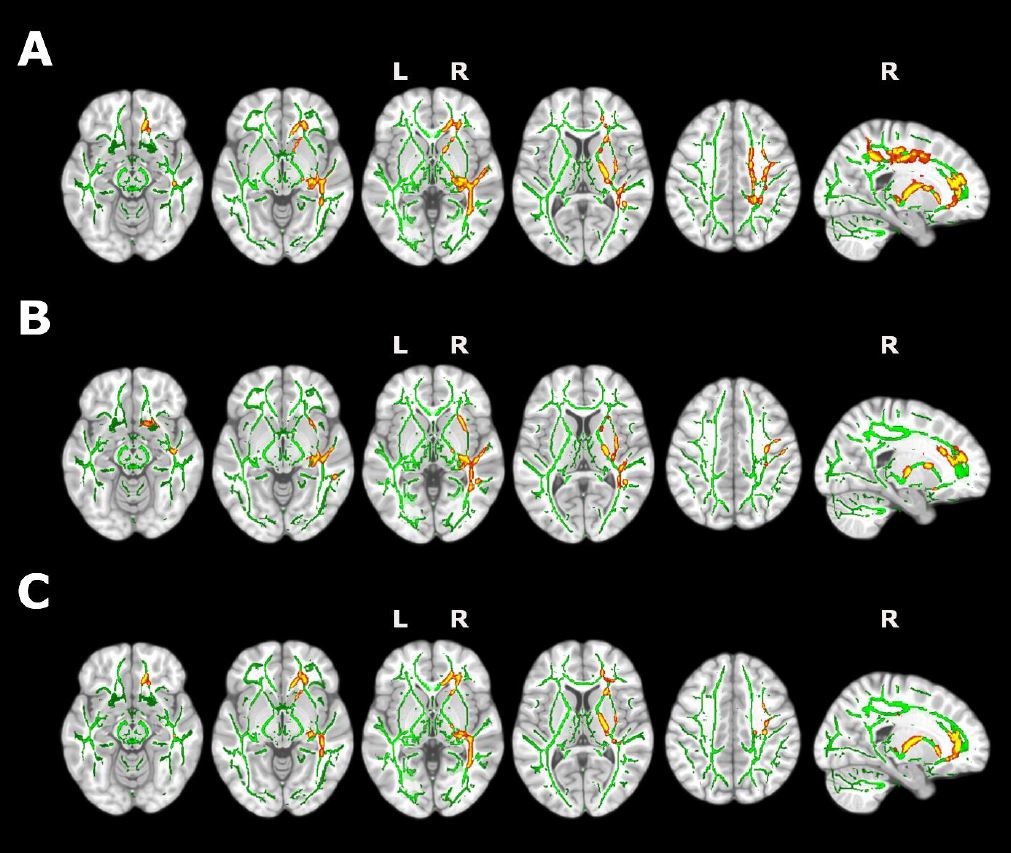

El presente estudio ha encontrado, además, cambios en la sustancia blanca cerebral mediante técnicas de resonancia magnética por difusión. “Estos hallazgos sugieren la presencia de procesos de inflamación cerebral que podrían tener un papel clave en la asociación entre la calidad del sueño y el Alzheimer”, destaca Oriol Grau, primer autor del estudio. De esta forma, la publicación de estos resultados abre la puerta a una nueva línea de investigación que hasta ahora no ha sido explorada para entender la relación entre la neuroinflamación, el sueño y la demencia.